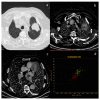

Dual-energy computed tomography (DECT) is one of the most promising technological innovations made in the field of imaging in recent years. Thanks to its ability to provide quantitative and reproducible data, and to improve radiologists' confidence, especially in the less experienced, its applications are increasing in number and variety. In thoracic diseases, DECT is able to provide well-known benefits, although many recent articles have sought to investigate new perspectives. This narrative review aims to provide the reader with an overview of the applications and advantages of DECT in thoracic diseases, focusing on the most recent innovations. The research process was conducted on the databases of Pubmed and Cochrane. The article is organized according to the anatomical district: the review will focus on pleural, lung parenchymal, breast, mediastinal, lymph nodes, vascular and skeletal applications of DECT. In conclusion, considering the new potential applications and the evidence reported in the latest papers, DECT is progressively entering the daily practice of radiologists, and by reading this simple narrative review, every radiologist will know the state of the art of DECT in thoracic diseases.